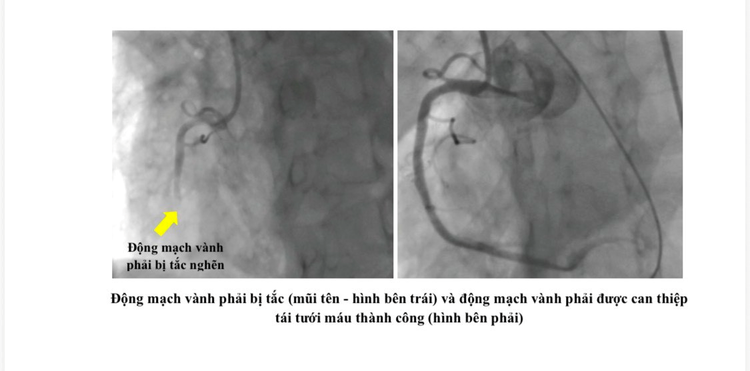

Tại đây, bệnh nhân được chụp mạch vành khẩn cấp và phát hiện có nhiều huyết khối gây tắc động mạch vành phải – là nguyên nhân chính gây ngưng tim trước nhập viện.

Các bác sĩ Khoa Hồi sức tim mạch của Bệnh viện Nhân dân Gia Định đã nhanh chóng đặt stent mạch vành và tiếp tục duy trì tuần hoàn ngoài cơ thể cho bệnh nhân. Hiện tại, bệnh nhân tỉnh táo, tiếp tục được theo hồi sức và dõi sát tại Khoa Hồi sức tim mạch.